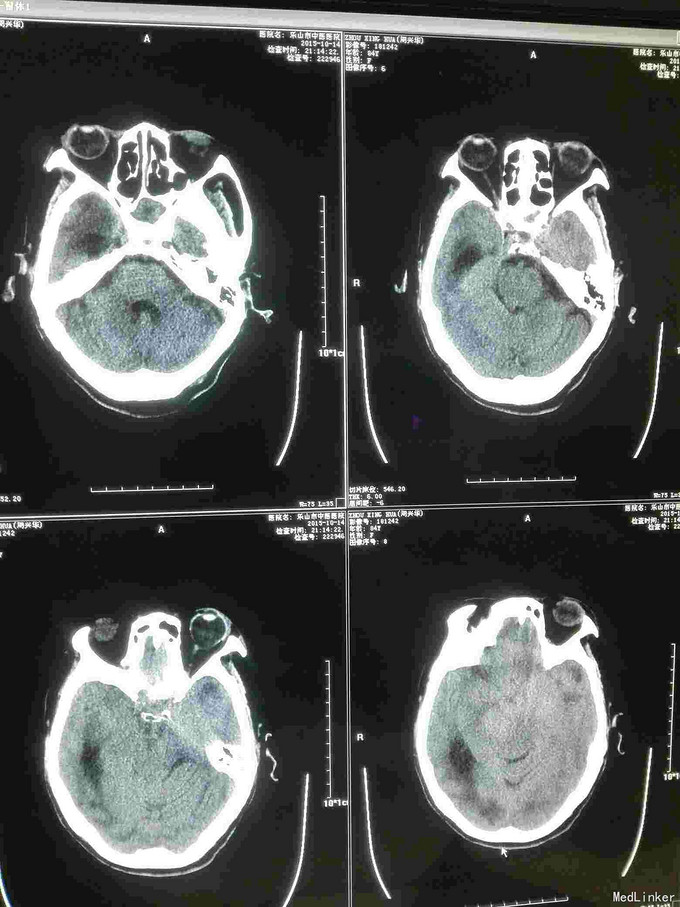

急诊CT病例

昏迷不醒就诊